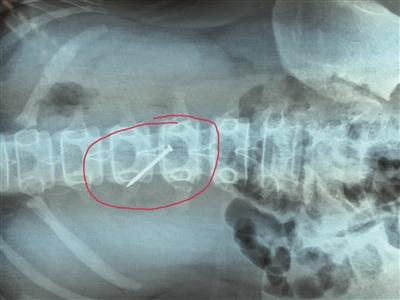

在淮安市妇幼保健院小儿外科的医生办公室里,记者见到了被取出来的铁钉,看上去铁钉已经生锈。从所拍摄的X光片中可以清晰地看出,这根铁钉取出之前在小轩的胃里的情况。据了解,小轩是泗阳县穿城镇一所学校的学生,平时寄宿在学校,27日晚,她的父亲突然接到老师的电话称,小轩在学校误吞了钉子,让他们赶紧带小轩去医院看。“我们先是去了镇上的医院,但是拍片子没有拍到,老师又让去县医院看。”小轩父亲告诉记者,到了县医院检查后,钉子确实在胃里,但是没有技术取出,只能带着孩子辗转到淮安就医,后来他们了解到,女儿是在学校被同学欺负,逼迫吞下铁钉,当老师发现时,已吞下,他们已向泗阳当地警方报警,目前他们正在查找铁钉来源。

据淮安市妇幼保健院主治医师王挺介绍,28日,当小轩来到该院时,只是表示上腹部稍微有点不适,有恶心的感觉,其他情况还好。通过给她拍片子、检查,医生起初并不认为她有穿孔的迹象。“我们没有贸然选择手术,而是让她留院观察,每隔一段时间拍摄一张X光片。”据王挺介绍,拍摄的多张X光片均显示铁钉一直停留在一个地方没有动。“我们判断这根铁钉极有可能卡在了某个地方或者已经刺破胃壁,没有自己排出的可能性,决定利用腹腔镜手术将铁钉取出。”

通过腹腔镜探查,医生发现在小轩第三腰椎处,钉子尾部穿过胃壁,插在了胆囊和肝脏之间,虽然已经出现了胃穿孔,但是钉子正好将穿孔处完全堵住,没有让胃液和气体淌出来,所以小轩并没有感到非常难受,如果钉子长时间留在胃里,将可能戳到大血管,危及生命。